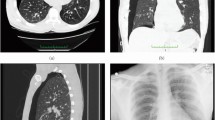

FigureĀ 5 shows the image reconstructions of a large-size breast (18.3Ā cm chest wall diameter). The compressed sensing method, Fast, total variation-Regularized, Iterative, Statistical Technique (FRIST24), suppresses the image noise in the central glandular tissue region. However, FRIST, using either of the two weighted FDK reconstructions as an initialization, further exacerbates the artifacts or inhomogeneities appearing in the weighted FDK reconstructions (columns 1ā2) as a result of severe data inconsistency and inefficacy of total variation regularization on image artifacts. In this large-size breast, one side of the breast skin near the chest wall is not fully reconstructed using our proposed method, as indicated by the yellow arrows in the coronal and axial images. It is worth noting that this side of the breast in the axial view is the most under-scanned for this simulated short-scan and offset-detector geometry, and the reconstruction of this region is more vulnerable to artifacts.

Image reconstructions of a large-size breast (18.3Ā cm chest wall diameter). Incomplete projection data were reconstructed using FDK with Parker weight, FDK with offset-detector weight (denoted as FDK-M), FRIST initialized using FDK with Parker weight, and FRIST initialized using FDK-M. The incomplete data were inpainted by AFN and further reconstructed by FDK-M. Complete projection data were reconstructed using FDK to obtain the reference (last column). The two FRIST methods further exacerbate the artifacts and/or inhomogeneities despite denoising the breast images. In our proposed method, the breast skin near the chest wall is not fully reconstructed (as indicated by the yellow arrows) since this region is the most under-scanned for the emulated short-scan and offset-detector geometry. The display window is [0.15, 0.35] cmā1.